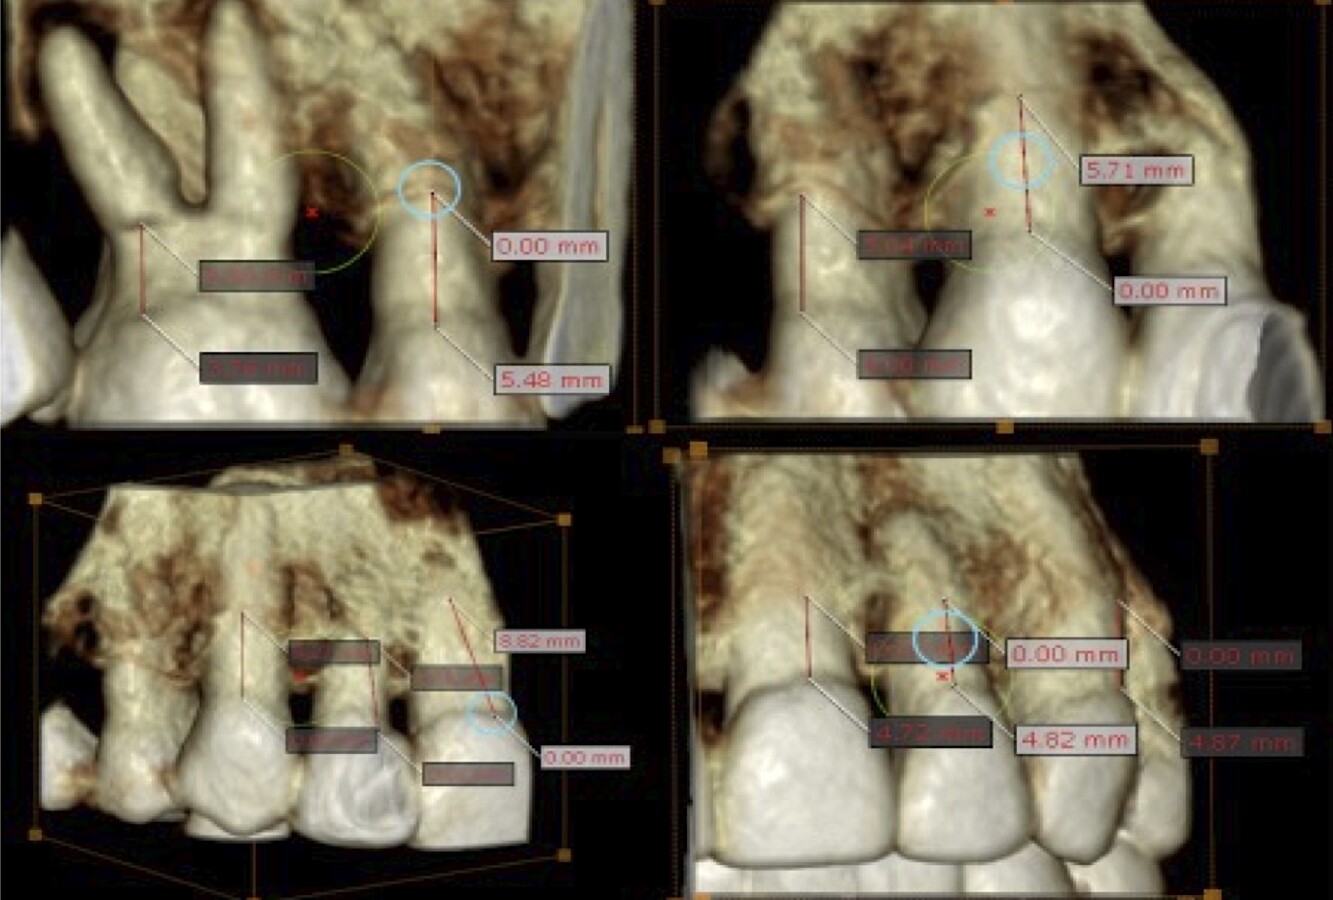

• Diagnóstico por imagen (CBCT)

El uso de tecnología tridimensional permite evaluar con precisión la extensión de las lesiones y planificar el tratamiento.

Figura 8. Diagnóstico visual 3D, medición y registro de los defectos.